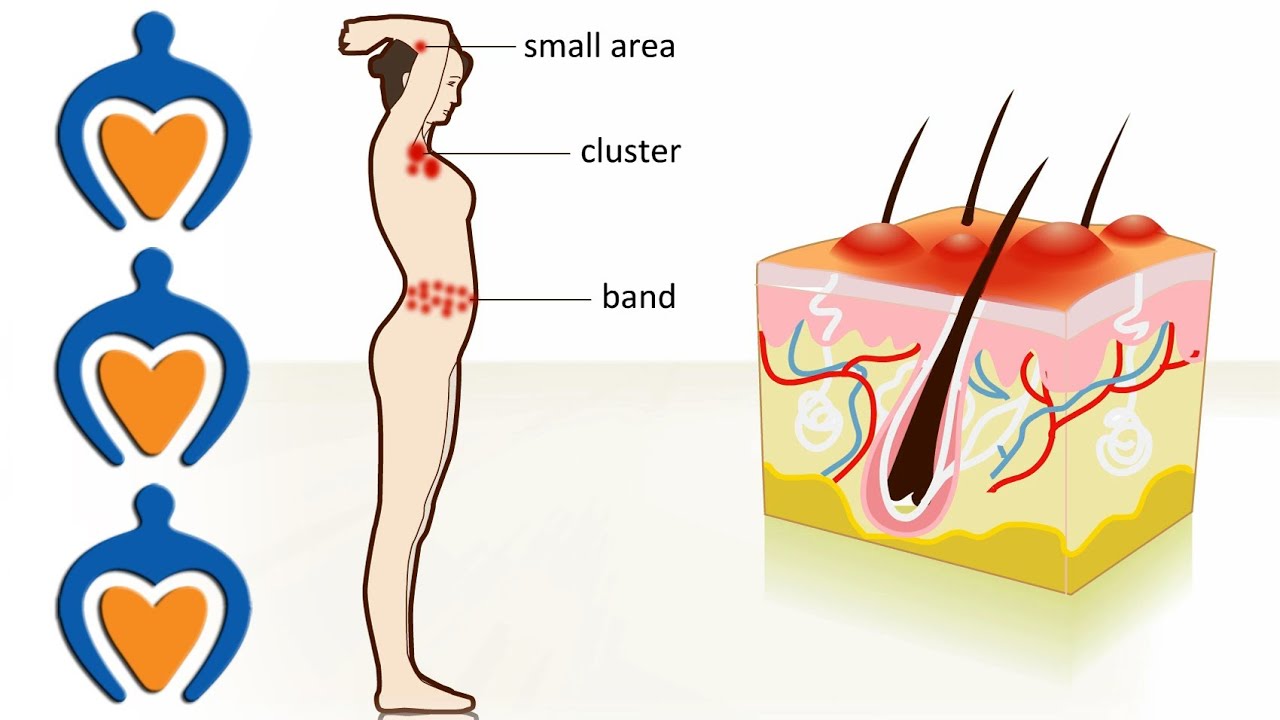

Shingles - The causes, symptoms, treatment and prevention

This animation explains what shingles is, what the symptoms are and where it can occur on your body. We also tell you when you should contact your family doctor and what kind of treatment options you have.